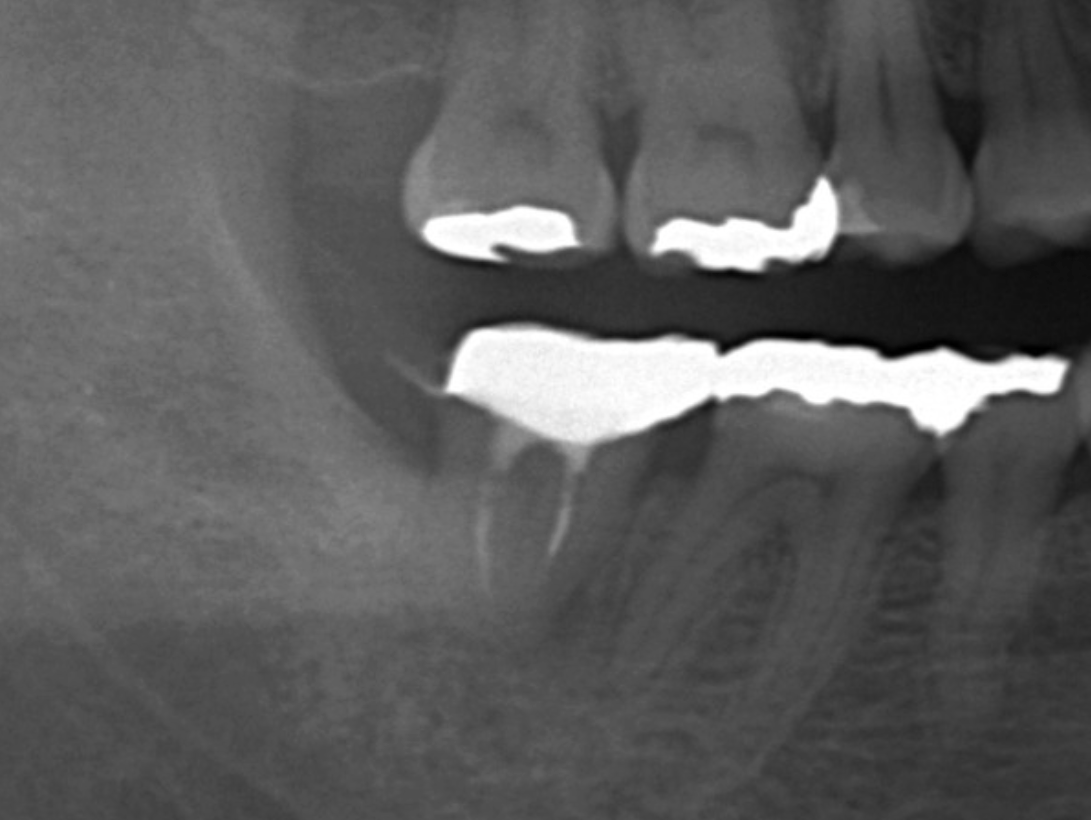

- 충치 제거 및 신경치료 여부 확인

- 치아 삭제 및 크라운 공간 확보

- 치아 본뜨기 또는 디지털 스캔

- 임시 크라운 장착

- 기공소에서 지르코니아 크라운 제작

- 완성된 크라운 장착 및 교합 조정

최근에는 디지털 스캔 장비를 사용해 치아 본을 뜨는 과정이 더 정밀해졌습니다. 이러한 기술 덕분에 크라운의 정확도와 적합도가 크게 향상되었습니다.